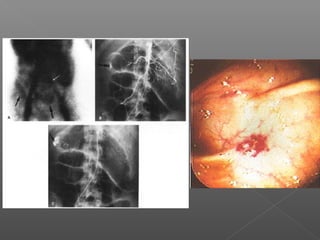

Clasificación de várices esofágicas

Grado I Grado II Grado III

Sociedad Japonesa para el estudio de la hipertensión portal.

 Grado 1: cordones que desaparecn con la

insuflación.

 Grado 2: cordones que se aplanan parcialmente

con la insuflación.

 Grado 3: ocupan menos del 50% de la luz.

 Grado 4: ocupan más de 50% de la luz.

Esclerosis

Ligadura endoscópica de varices esofágicas.

Ligadura